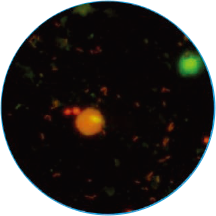

免疫荧光法结果展示及判读示例

阴道分泌物多重免疫荧光染色技术,具备形态学与荧光学的双重优势。可以同时对上皮细胞,白细胞,乳酸杆菌,线索细胞,念珠菌和毛滴虫等进行染色区分,既能检测阴道相关病原体感染,也能评估其阴道微生态和阴道清洁度等是否正常,为临床的快速诊断和治疗提供帮助。

念球菌

橙红色荧光

孢子形态直径3-6 μm

明显大于细菌,小于滴虫

毛滴虫

橙黄色荧光

梨形或椭圆形,直径

10~13 μm稍大于白细胞